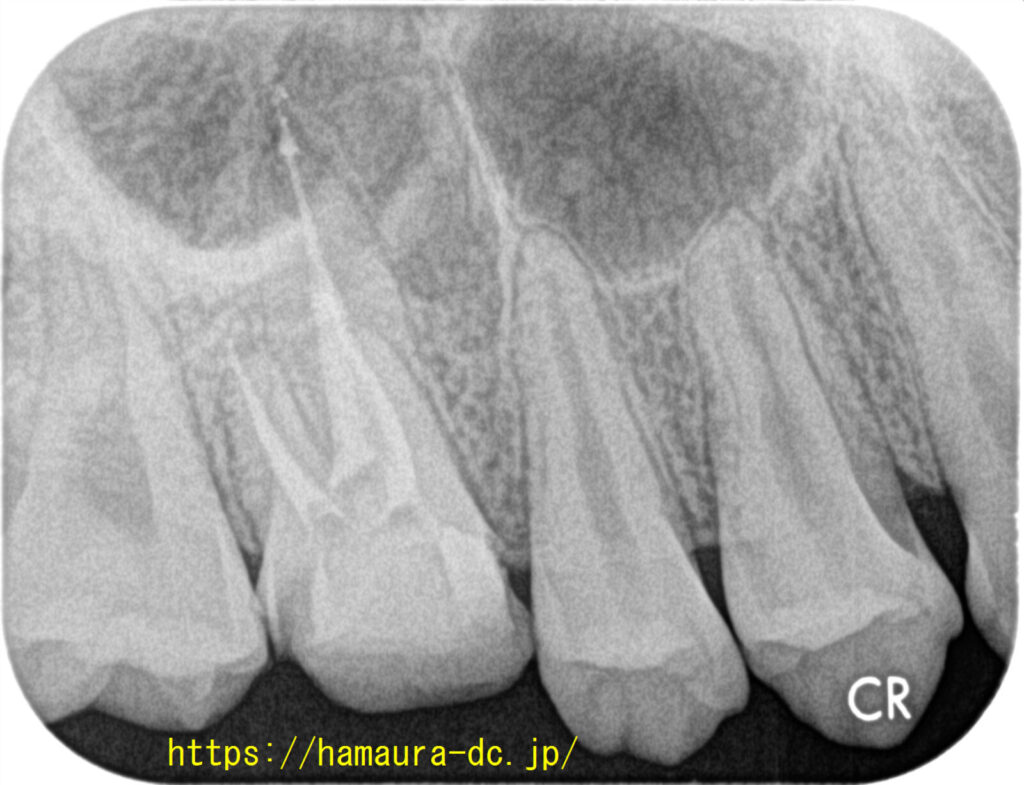

再発を防ぎ、抜歯のリスクを抑える精密根管治療

「再発する」というのイメージが強い根管治療。

当院の根管治療は再発しにくいのが特徴。